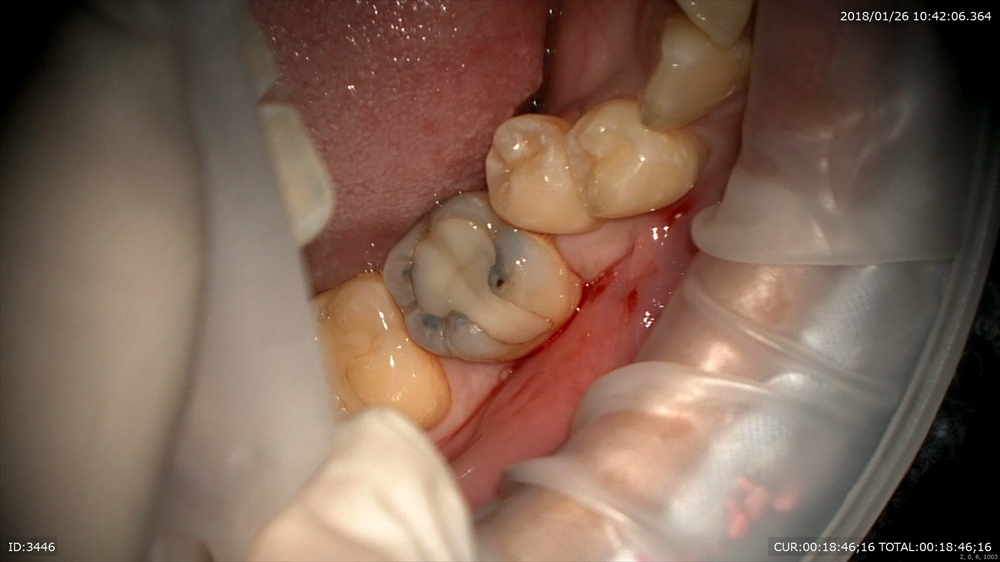

次の方。一見ちょっと黒いけど。。。。歯科ドックで発覚しました。この下にむし歯があります。

ギャー!!!ドックやってよかった。